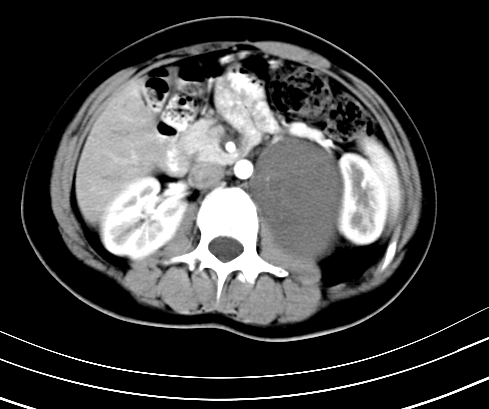

动脉期